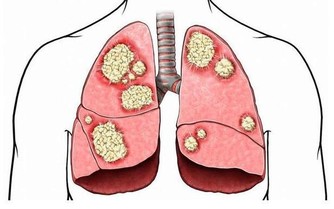

但由於不少婦女擔心荷爾蒙治療可能致癌,一聽到荷爾蒙治療就萌生退意。

李奇龍強調,「更年期治療已有多重選擇,不是每一種治療都有高致癌風險」。

他進一步說明道,長期服用恐增加心血管疾病與乳癌發生風險的為傳統荷爾蒙治療,

但目前更年期治療多是採用新一代「類荷爾蒙」治療,可以改善症狀,又不過度刺激乳房與子宮內膜,

「婦女朋友不用過度擔心,應遵醫囑把握黃金治療時間,更年期生活一樣可以過得青春和健康。」